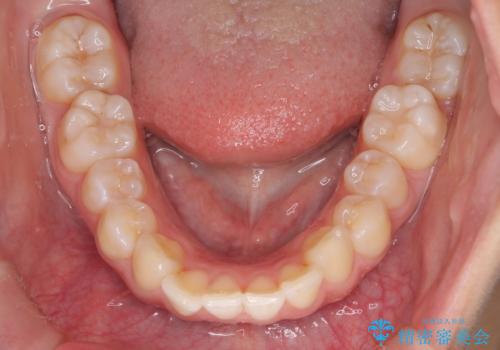

- ハーフリンガル

- 3年1ヶ月

- 出っ歯を治したいとのことで来院されました。

目立たない装置が希望とのことでハーフリンガルで治療をすることとしました。